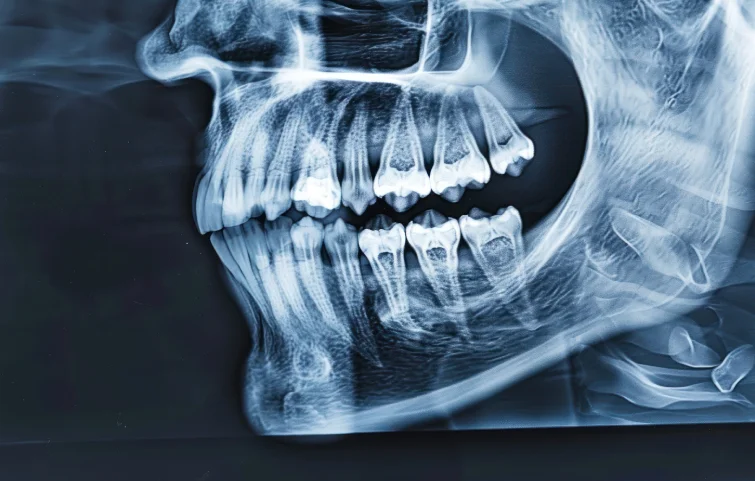

Jaw fractures, particularly of the mandible or maxilla, are commonly caused by trauma from accidents, sports injuries, or violence. Diagnosis begins with a thorough clinical evaluation. The patient may present with facial swelling, bruising, pain, difficulty in opening or closing the mouth, malocclusion (improper bite), and numbness due to nerve involvement.

Physical examination includes assessing jaw alignment, mobility, and palpation for stepoffs or crepitus. Intraoral examination checks for bleeding, lacerations, or tooth mobility. Imaging is crucial for confirmation. A panoramic X-ray (orthopantomogram) is a common initial tool to visualize the mandible. However, computed tomography (CT) scans are the gold standard for complex fractures or midface injuries, providing detailed 3D visualization of bone involvement.

In some cases, cone-beam CT (CBCT) may be used, especially in dental settings, to assess smaller or localized fractures. If the fracture involves the condyle or temporomandibular joint, additional TMJ-specific views may be needed. Associated injuries such as dental fractures or airway compromise should also be evaluated.

Treatment decisions are guided by imaging findings, location of the fracture (e.g., angle, symphysis, condyle), displacement, and patient symptoms. The goal of diagnosis is not only to confirm the fracture but also to assess complications, such as infection, nerve damage, or airway obstruction, ensuring timely and appropriate surgical or non-surgical intervention.